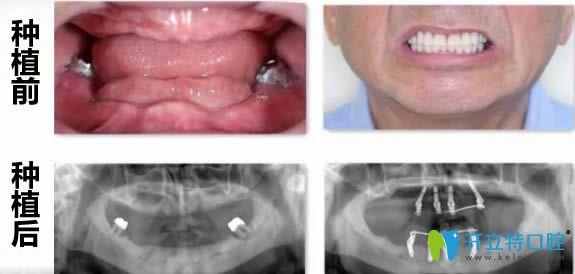

【本院全口牙缺失即刻種植案例圖】:

洛陽(yáng)拜博口腔全口牙缺失即刻種植案例圖